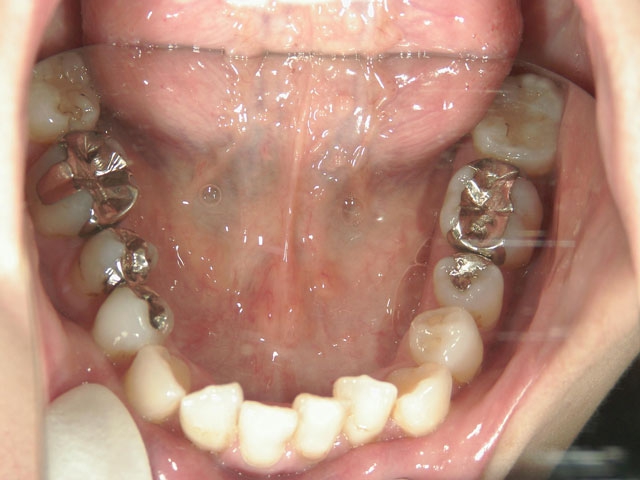

矯正歯科 治療後矯正歯科 全顎ワイヤー矯正 治療後矯正歯科(全顎ワイヤー矯正)治療後

28歳女性 浜松市中区在住

治療期間2年6ヶ月

矯正歯科 治療前 外科手術併用(コルチコトミー)、非抜歯